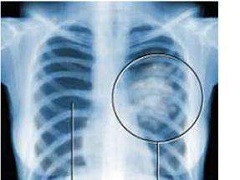

肺癌的早期症状有哪些。众所周知,肺癌的死亡率非常高,因此人们都非常担心会患上肺癌这种疾病,肺癌的发生会给患者带来的是无尽的痛苦,但是如果我们能够及时的发现肺癌疾病的症状的话,我们就可以及时的进行治疗,减少伤害,下面海得康PD-1代购带您一起了解一下肺癌的早期症状有哪些吧!

咳嗽:非常常见的肺癌的早期的症状就是咳嗽,很多的人都会吧咳嗽这种这种忽略掉,因为咳嗽的症状是非常的常见的,肺部出现刺激性干咳或者是原有咳嗽的性质发生了极大的改变。这都可能是因为肺部恶性肿瘤的病灶造成了支气管痉挛而导致的。咳嗽是早期肺癌的主要症状之一。

胸痛:还有当患者患上肺癌的时候,患者的胸部会出现疼痛,或者连续,或者间歇,而且疼痛的程度也不一样,患者胸痛的疼痛程度是有一定区别的,而且这种区别不仅取决病情的严重程度,还取决于患者具体的个体素质。

咳血:还有比较明显的肺癌的症状,就是咳血。在咳嗽的时候,患者了能会出现咳血的症状,这时候患者就需要注意了。该症状主要是由于肿瘤细胞侵犯了支气管的黏膜所造成的,只是可能由于患者不同的机体素质而导致病情程度的深浅不同,而痰中血丝表现也不尽相同,随着病情的不断加重,一旦肿瘤细胞浸润到血管,就会造成大咳血,甚而危及患者的生命。